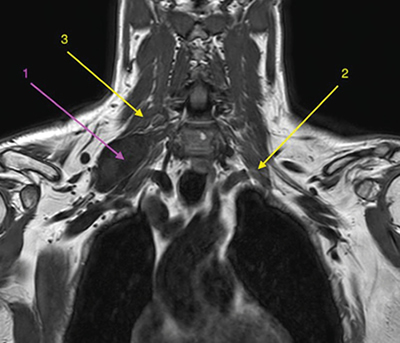

Con la orientación diagnóstica inicial de schwannoma de plexo braquial derecho con escasa repercusión clínica, se decidió actitud expectante. Se instauró tratamiento analgésico de primer escalón y ansiólisis a demanda para dormir. El paciente era reticente al tratamiento neuromodulador debido a sus efectos secundarios. Seis meses después, tras una nueva RM de control, se observó un discreto crecimiento de la lesión con probable efecto compresivo por los músculos escalenos anterior y medio (Figuras 1 y 2). Se indicó una infiltración diagnóstico-terapéutica con toxina botulínica tipo A (Botox®) ecodirigida. Las crisis de dolor eran más frecuentes y de más minutos de duración y empezaban a afectar su calidad de vida. EVA 2-3 en reposo, 8-9/10 en las crisis.

Fig. 1. RM coronal en T1. 1. Schwannoma de plexo braquial derecho. 2. Músculo escaleno anterior izquierdo, para mostrar su ubicación relativa al plexo braquial ipsilateral, dado que en el lado derecho no se identifica claramente. 3. Músculo escaleno medio derecho